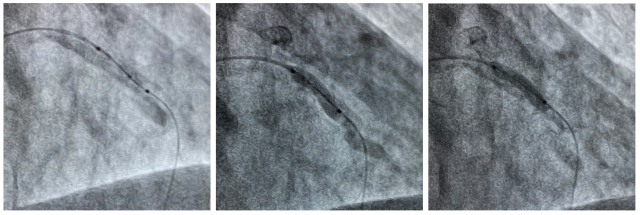

Guidezilla支持下通过Shockwave球囊 / 初始Shockwave不能完全膨胀 / 冲击治疗后Shockwave球囊完全膨胀